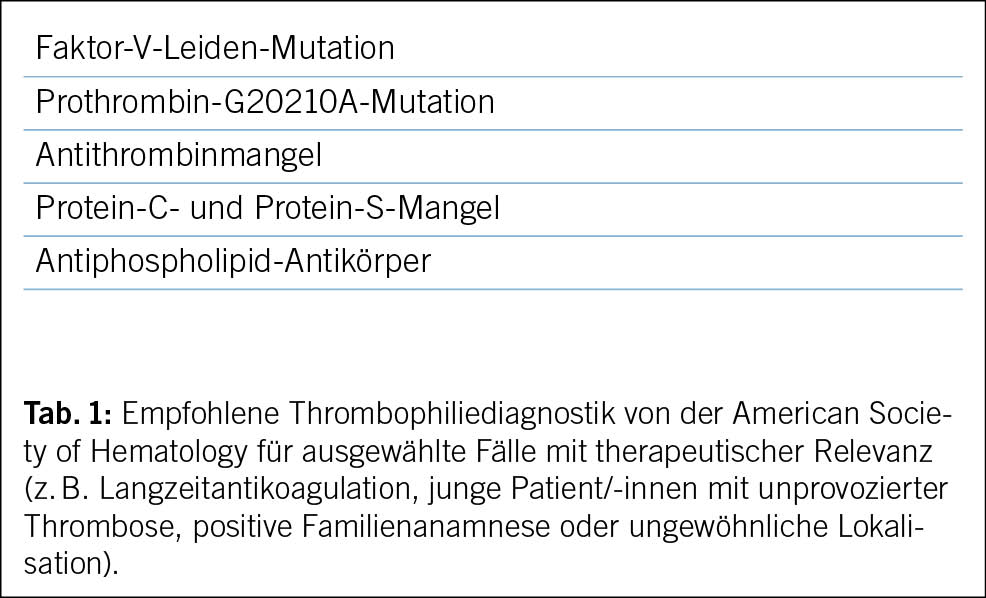

In der Literatur werden Thrombosen der Vena jugularis sowie Armthrombosen (V. subclavia, V. axillaris, V. brachialis) in primäre und sekundäre Thrombosen unterteilt, wobei diese Einteilung international nicht einheitlich definiert ist (4). Primäre Thrombosen der oberen Extremitäten entstehen entweder im Rahmen eines Thoracic-outlet-Syndroms (TOS) oder idiopathisch. Bei unserem Fall waren weder anamnestische noch radiologische Hinweise auf ein TOS zu finden. Nach aktuellen Studien wird bei etwa 25 % der Patienten mit idiopathischer Thrombose innerhalb eines Jahres eine maligne Neoplasie diagnostiziert, und bei 25–42 % wurde eine Hyperkoagulabilität festgestellt (5). Diese Zahlen unterstreichen die Notwendigkeit einer gründlichen Ursachensuche bei der Diagnostik von atypischen Thrombosen, insbesondere auch einer Thrombophilieabklärung (Tab. 1) (6).